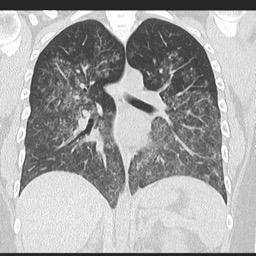

o Nagy felbontású CT (HRCT): Diffúz üveges elhomályosodásokat és hemosziderin lerakódásokat mutat

o HRCT: intersticiális tüdőbetegséget és üveges elhomályosodásokat mutat

o HRCT: Diffúz üveges elhomályosodás és alveoláris konszolidáció.

Vasculitis okozta diffúz alveoláris vérzés

Forrás: radiopaedia.org